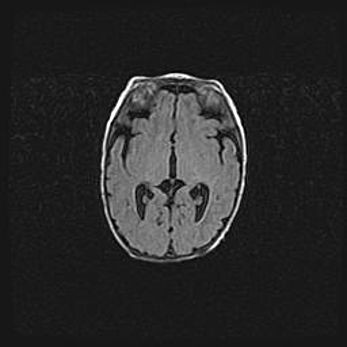

Наружная гидроцефалия с возможной атрофией височных областей.

Возраст: 28 дней

Вес: 3670 г

Пол: мужской

Окружность головы: 38 см

Срок гестации: 40 недель

Гидроцефалия головного мозга у новорожденных – это заболевание, которое характеризуется скоплением избыточного количества спинномозговой жидкости в желудочковой системе головного мозга в результате затруднения её перемещения от места выработки к месту поглощения в кровеносную систему или вследствие нарушения абсорбции. При открытой наружной форме гидроцефалии у новорожденных расширяются и переполняются субарахноидные пространства.

При нормотензивных  формах,  которые,  как  правило,  являются  следствием  перенесенных ишемических  повреждений  паренхимы  мозга,  возможно  сочетание микроцефалии  с нормотензивной гидроцефалией. В основе данных изменений лежит атрофия больших полушарий с преимущественной  локализацией  в  лобно-височных  областях.